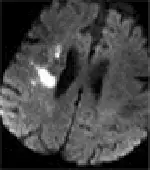

附圖為何種 MR影像?

- 影像品質與假影:此為腦部軸切面(axial view)MRI 影像。畫面呈現較低的空間解析度(low spatial resolution)與明顯的顆粒感,這是回音平面造影(Echo-Planar Imaging, EPI)技術的典型特徵。

- 背景組織與液體訊號:兩側側腦室內的腦脊髓液(CSF)呈現低訊號(暗色)。

- 病灶特徵:在右側大腦半球(corona radiata / centrum semiovale 區域周邊)可見一處極為明顯的局部高訊號(亮色)病灶。此特徵在臨床上高度提示該區域發生了「限制性擴散」(restricted diffusion),為急性缺血性中風引發細胞毒性水腫(cytotoxic edema)的經典表現。

- (A) DWI(diffusion weighted imaging):正確。DWI 常用 EPI 序列擷取,因此影像具備較粗糙的顆粒感與略微的幾何形變。在 DWI 中,自由擴散的水分子(如腦室內的 CSF)會快速失去相位而呈現